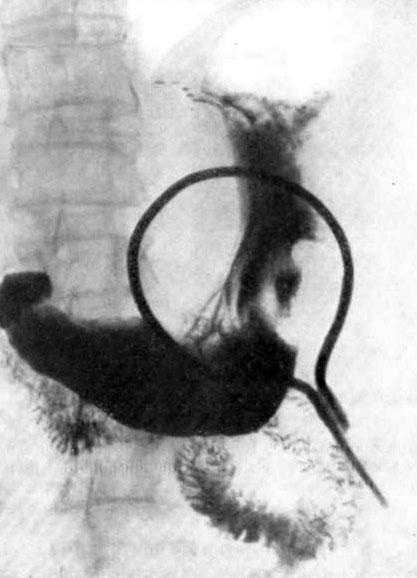

Современные технологии в медицине: рентгенодиагностика заболеваний желудка

Раздел: Фотогалерея мыслей